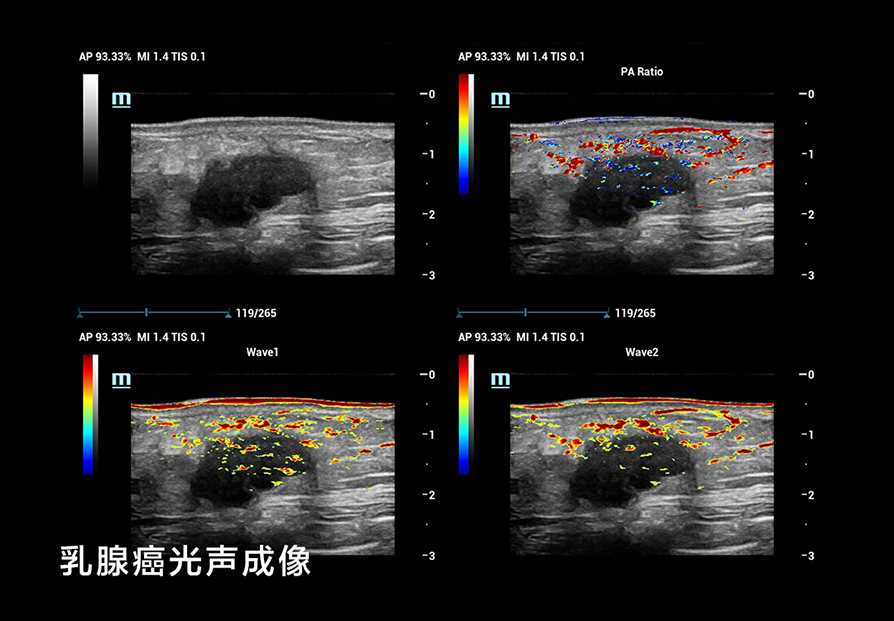

我们在 B-Mode 成像方面考虑了更细(超高频率)、更深(超低频率),更好的对比分辨率,如个异化的 HD Scope,以提高早期鉴别诊断的能力;在超微血流方面, UMA突破传统彩色多普勒的限制,使细微血流的显示达到新的高度;还有创新的血流流变学(VFM)等分析技术,以及流变学与生物力学结合的技术等;在弹性成像方面,我们也有很多可圈可点的地方。我们可以形成多模态,多模式的成像与显示,为临床和科研提供新的工具;在造影成像(CEUS)方面,我们还有极具特色的高帧率造影技术和 CEUS QI 分析系统,还有光声成像等这些新的方向。

我们还用了一个技术,在医院里看到乳腺病灶类的微钙化灶,这些极小的微钙化灶,原来超声是看不见的,只有钼靶才能看到。但能看见微钙化灶对乳腺癌的早期鉴别诊断至关重要。钼靶在乳腺微钙化灶方面有非常细的分类,对早期鉴别诊断提供了非常有意义的指导作用。如果我们持续发展这个超声技术,把它用在日常的临床工作中,那医生就能够更早地发现乳腺病灶的早期微钙化。